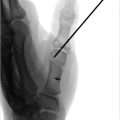

Plain radiographs in the PA, lateral, and oblique views can reveal a diastasis between the scaphoid and lunate. Greater than 3 to 4 mm gapping may offer the appearance of a “Terry Thomas sign.” On the lateral view, the SL angle is a line drawn between the long axis of the scaphoid and lunate on the lateral X-ray view. Normally, this angle measures between 30 to 60 degrees. Given the propensity of the scaphoid to flex in the absence of a competent SLIOL, the SL angle on the lateral film will be increased > 60 degrees. This is termed dorsal intercalated segmental instability (DISI) (► Fig. 67.2). Provocative radiographs such as PA clench or scaphoid X-rays can also accentuate the radiographic malalignment.